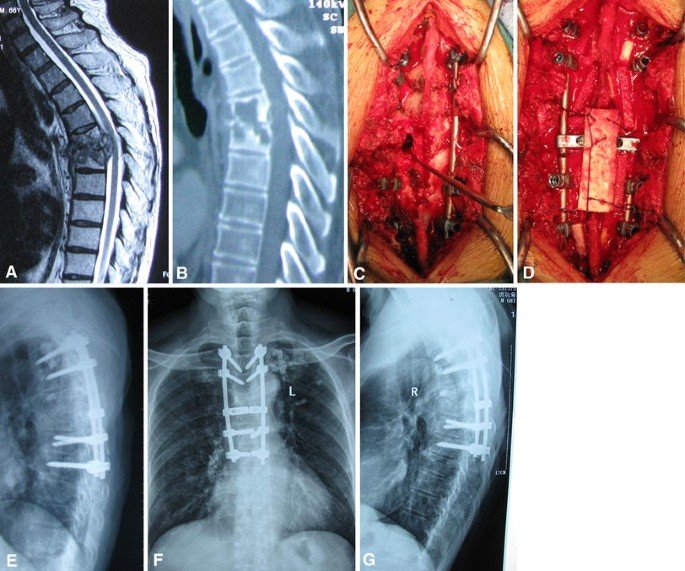

Furthermore, early diagnosis and intervention are crucial to prevent spinal instability, neurological deficits, or permanent disability. Advanced imaging techniques, including MRI and CT scans, allow precise identification of infection location and extent. Consequently, patients receive tailored surgical or medical management that ensures the best outcomes.

Accurate diagnosis of spinal TB is critical for successful management. Firstly, the clinic performs a detailed clinical examination, assessing pain, mobility, and neurological function. Moreover, advanced imaging, including MRI, CT scans, and X-rays, helps determine the extent of vertebral destruction, abscess formation, and spinal alignment.

Surgery becomes necessary when spinal instability, neurological deficits, severe deformity, or abscess formation occurs. Firstly, Dr. Gadkari performs debridement and stabilization procedures to remove infected tissue and restore vertebral alignment. Moreover, minimally invasive and endoscopic techniques reduce incision size, tissue trauma, and recovery time.

In addition, spinal instrumentation, including pedicle screws and rods, provides stability while promoting bone healing. Consequently, patients experience pain relief, improved mobility, and protection from further deformity. Furthermore, careful planning ensures preservation of neurological function and reduces postoperative complications.

Additionally, advanced imaging guidance enhances precision during surgery, ensuring optimal outcomes and long-term spinal health.

Technology and Surgical Precision

Advanced technology ensures safe and effective spine surgery for TB. For example, intraoperative imaging, laser-assisted tools, and minimally invasive instruments allow precise removal of infected tissue. Moreover, real-time guidance helps place instrumentation accurately, preserving healthy structures.